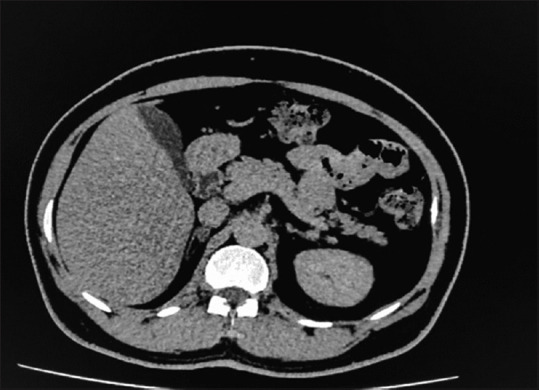

Conn's syndrome or primary aldosteronism (PA) due to aldosterone-producing adrenal adenoma (APA) is the most frequent cause of hypokalemia and secondary hypertension. We are reporting a Primary Aldosteronism(PA) case in an indian male, who presented with recurrent lower limb weakness & was admitted twice for management of his symptoms. On evaluating, laboratory reports revealed that his symptoms are due to refractory severe hypokalemia, metabolic alkalosis, raised serum aldosterone levels, and low plasma renin activity. Transtubular potassium gradient (TTKG) was suggestive of ongoing renal potassium loss. Computed Tomography (CT) angiography of adrenal glands during his first admission showed an 8-mm nodule in the right adrenal gland. CT angiography during his second admission with more severe similar complaints revealed an increase in the size of this nodule. The patient was managed with serum potassium correction and surgical intervention. He underwent laparoscopic right adrenalectomy. Following the surgery, the patient serum potassium normalized and he had a good clinical outcome. We suggest clinicians to consider screening for PA and offer surgical intervention wherever necessary in cases with refractory hypokalemia and secondary hypertension.